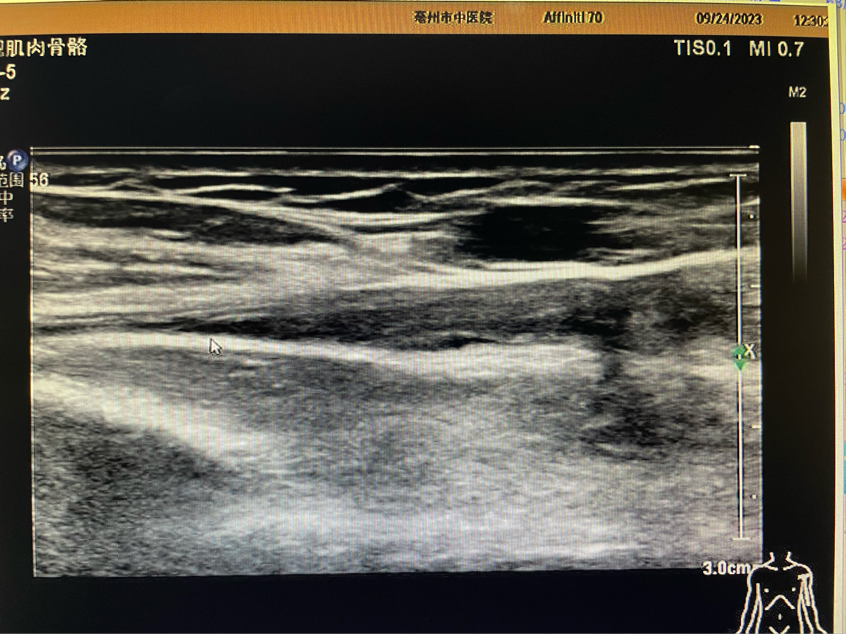

肌骨超声检查是我院超声科新开展的检查项目。超声科刘刚医生为患者进行详细肌骨超声检查,检查所见:左侧肱骨头大小结节间沟空虚,代之以液性暗区,较厚处约1.5mm,肱二头肌长头肌腱连续性中断,断端远端挛缩,周围可见厚约3.6mm液性暗区。检查意见:左侧肱二头肌长头肌腱完全断裂伴周围积液。